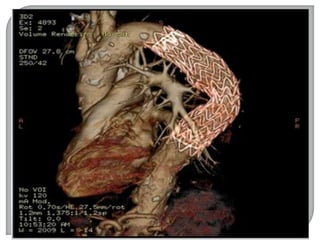

-TOMOGRAFIA COMPUTADORIZADA

 Em 1967, iniciaram-se as 11 pesquisas sobre

reconhecimento de imagens e técnicas de

armazenamento de dados em um computador.

 Em 1971 foi realizado o primeiro teste de um

“SCANNER” do crânio, num hospital de Londres.

 O scanner foi apresentado oficialmente em 1972.

 A.M Comark (Físico norte americano) e Geoffrey

Hounsfield (engenheiro inglês).

 EMI primeira empresa a fabricar o scanner.

Gravadora de discos (Beatles).

 Reconhecidos como TOMÓGRAFOS

COMPUTADORIZADOS.

 Em 1979, estes dois cientistas receberam o

prêmio Nobel.